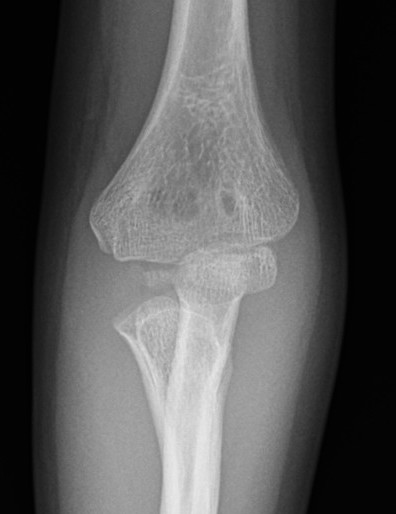

Case 1. Missed Monteggia, injury 6 months ago